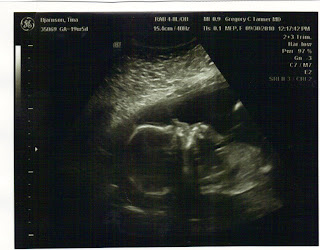

Oaklee's head and body.

Oaklee's head and body